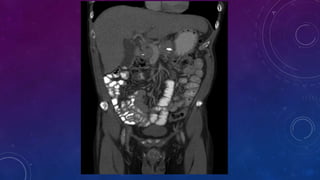

• Multiple pelvic phleboliths.

• Small well-defined round osseous lesions in the left

side of the abdomen, adjacent to midline represent

calcified lymph node in the para-aortic and left

common iliac groups, also visualized on the

corresponding CT.